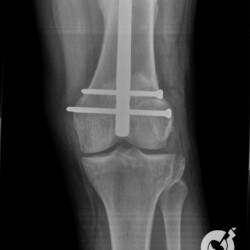

Fratura da patela com importante desvio e fratura cominutiva do 1/3 proximal da tíbia comprometendo a eminência intercondiliana.